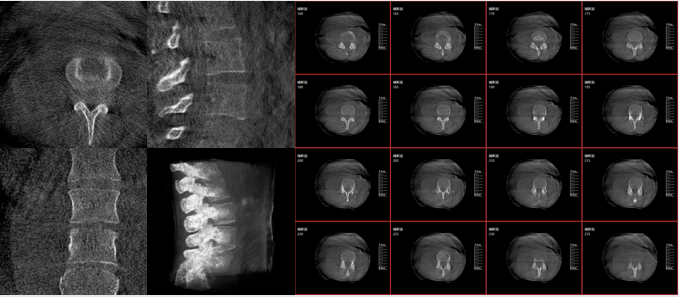

術(shù)中三維影像

而三維影像的MPR圖像組可以通過不同平面的切分,使成像區(qū)內(nèi)更豐富的信息得以呈現(xiàn)。尤其是二維影像無法涉及的橫斷面,提供了另一個空間維度的信息量。

作為使用者,醫(yī)生在手術(shù)中雖然有術(shù)前的影像作為判定依據(jù),但每一臺手術(shù)都具有獨特性,需要術(shù)中三維影像提供的實時信息,作為術(shù)中診療操作的基礎(chǔ)。

在MPR圖像中,冠狀面、矢狀面和橫斷面的信息大大提高了醫(yī)生對于病灶區(qū)以及手術(shù)效果的判定。